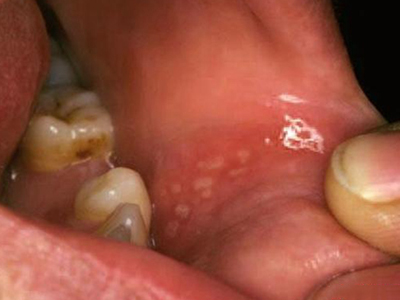

口腔

溃疡

创伤性溃疡磨牙旁边的肉被磨烂了图

创伤性溃疡发生在上牙膛靠近磨牙处的黏膜面,表面已经被磨烂,是因牙齿长期刺激所致,溃疡形态不规整,破溃的黏膜发白,继续刺激会扩大创面。